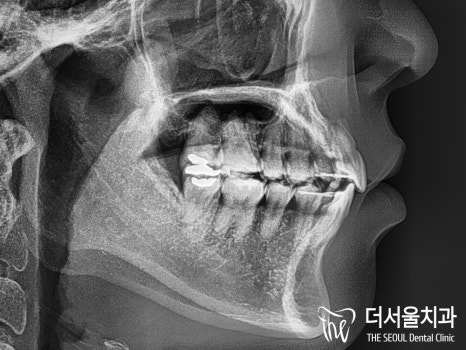

바로 옆에서 찍은 세팔로(Ceph) 사진을

보여드리겠습니다.

노란색으로 그은 선이 바로 ‘리케츠라인’ 입니다.

코 끝과 턱 끝을 이은 가상의 선인데

여기를 기준으로 입술이 튀어나와 있으면

‘돌출입’ 이라 할 수 있습니다.

많이 튀어나와 있는 것을 볼 수 있습니다.

이에 따라, 앞니들도 앞쪽으로 뻐드러져 있습니다.